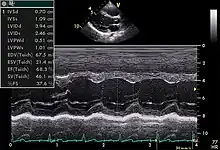

![]() An abnormal echocardiogram: Image shows a midmuscular ventricular septal defect. The trace in the lower left shows the cardiac cycle and the red mark the time in the cardiac cycle when the image was captured. Colors are used to represent the velocity and direction of blood flow. | |